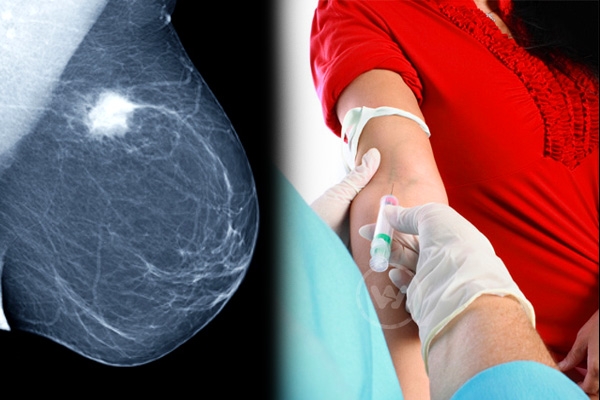

(Image source from: Blood Test to Predict the Risk of Breast Cancer!})

Women of both developed and less developed states are victims of the breast cancer, which is remaining horrific for the families of the victims. According to a study that was published in Metabolomics, a new type of blood test could predict the possibility of getting the risk in coming 2-5 years.

The new method would benefit most of the women in long-term with precautions. So far mammography was one of the diagnosing methods to detect the presence of cancer in breasts. The mammography could able to diagnose the newly developed breast cancer with a sensitivity of 75 per cent, while new blood test is claimed to be maintaining the sensitivity of 80 percent.